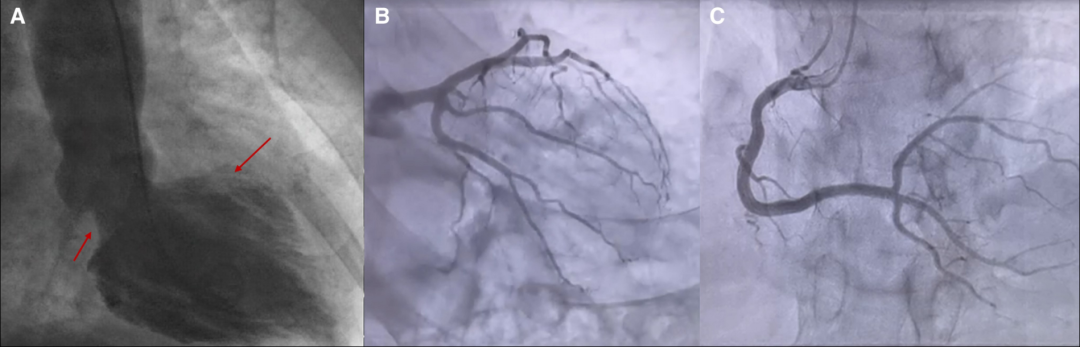

初始经胸超声心动图示左室肥厚,射血分数保留(58%),但心室基底部及中间段运动减弱。左心室造影确认基底部及中间段无运动、心尖部运动正常,符合反向Takotsubo心肌病特征(图1A);冠状动脉造影未见显著狭窄(图1B,C)。

图1心脏室壁显像显示倒置(基底)takotsubo心肌病的特征性模式,顶段超动,基底左室壁运动减慢(A,箭头)。冠状动脉造影未显示阻塞性冠状动脉疾病(B和C)。